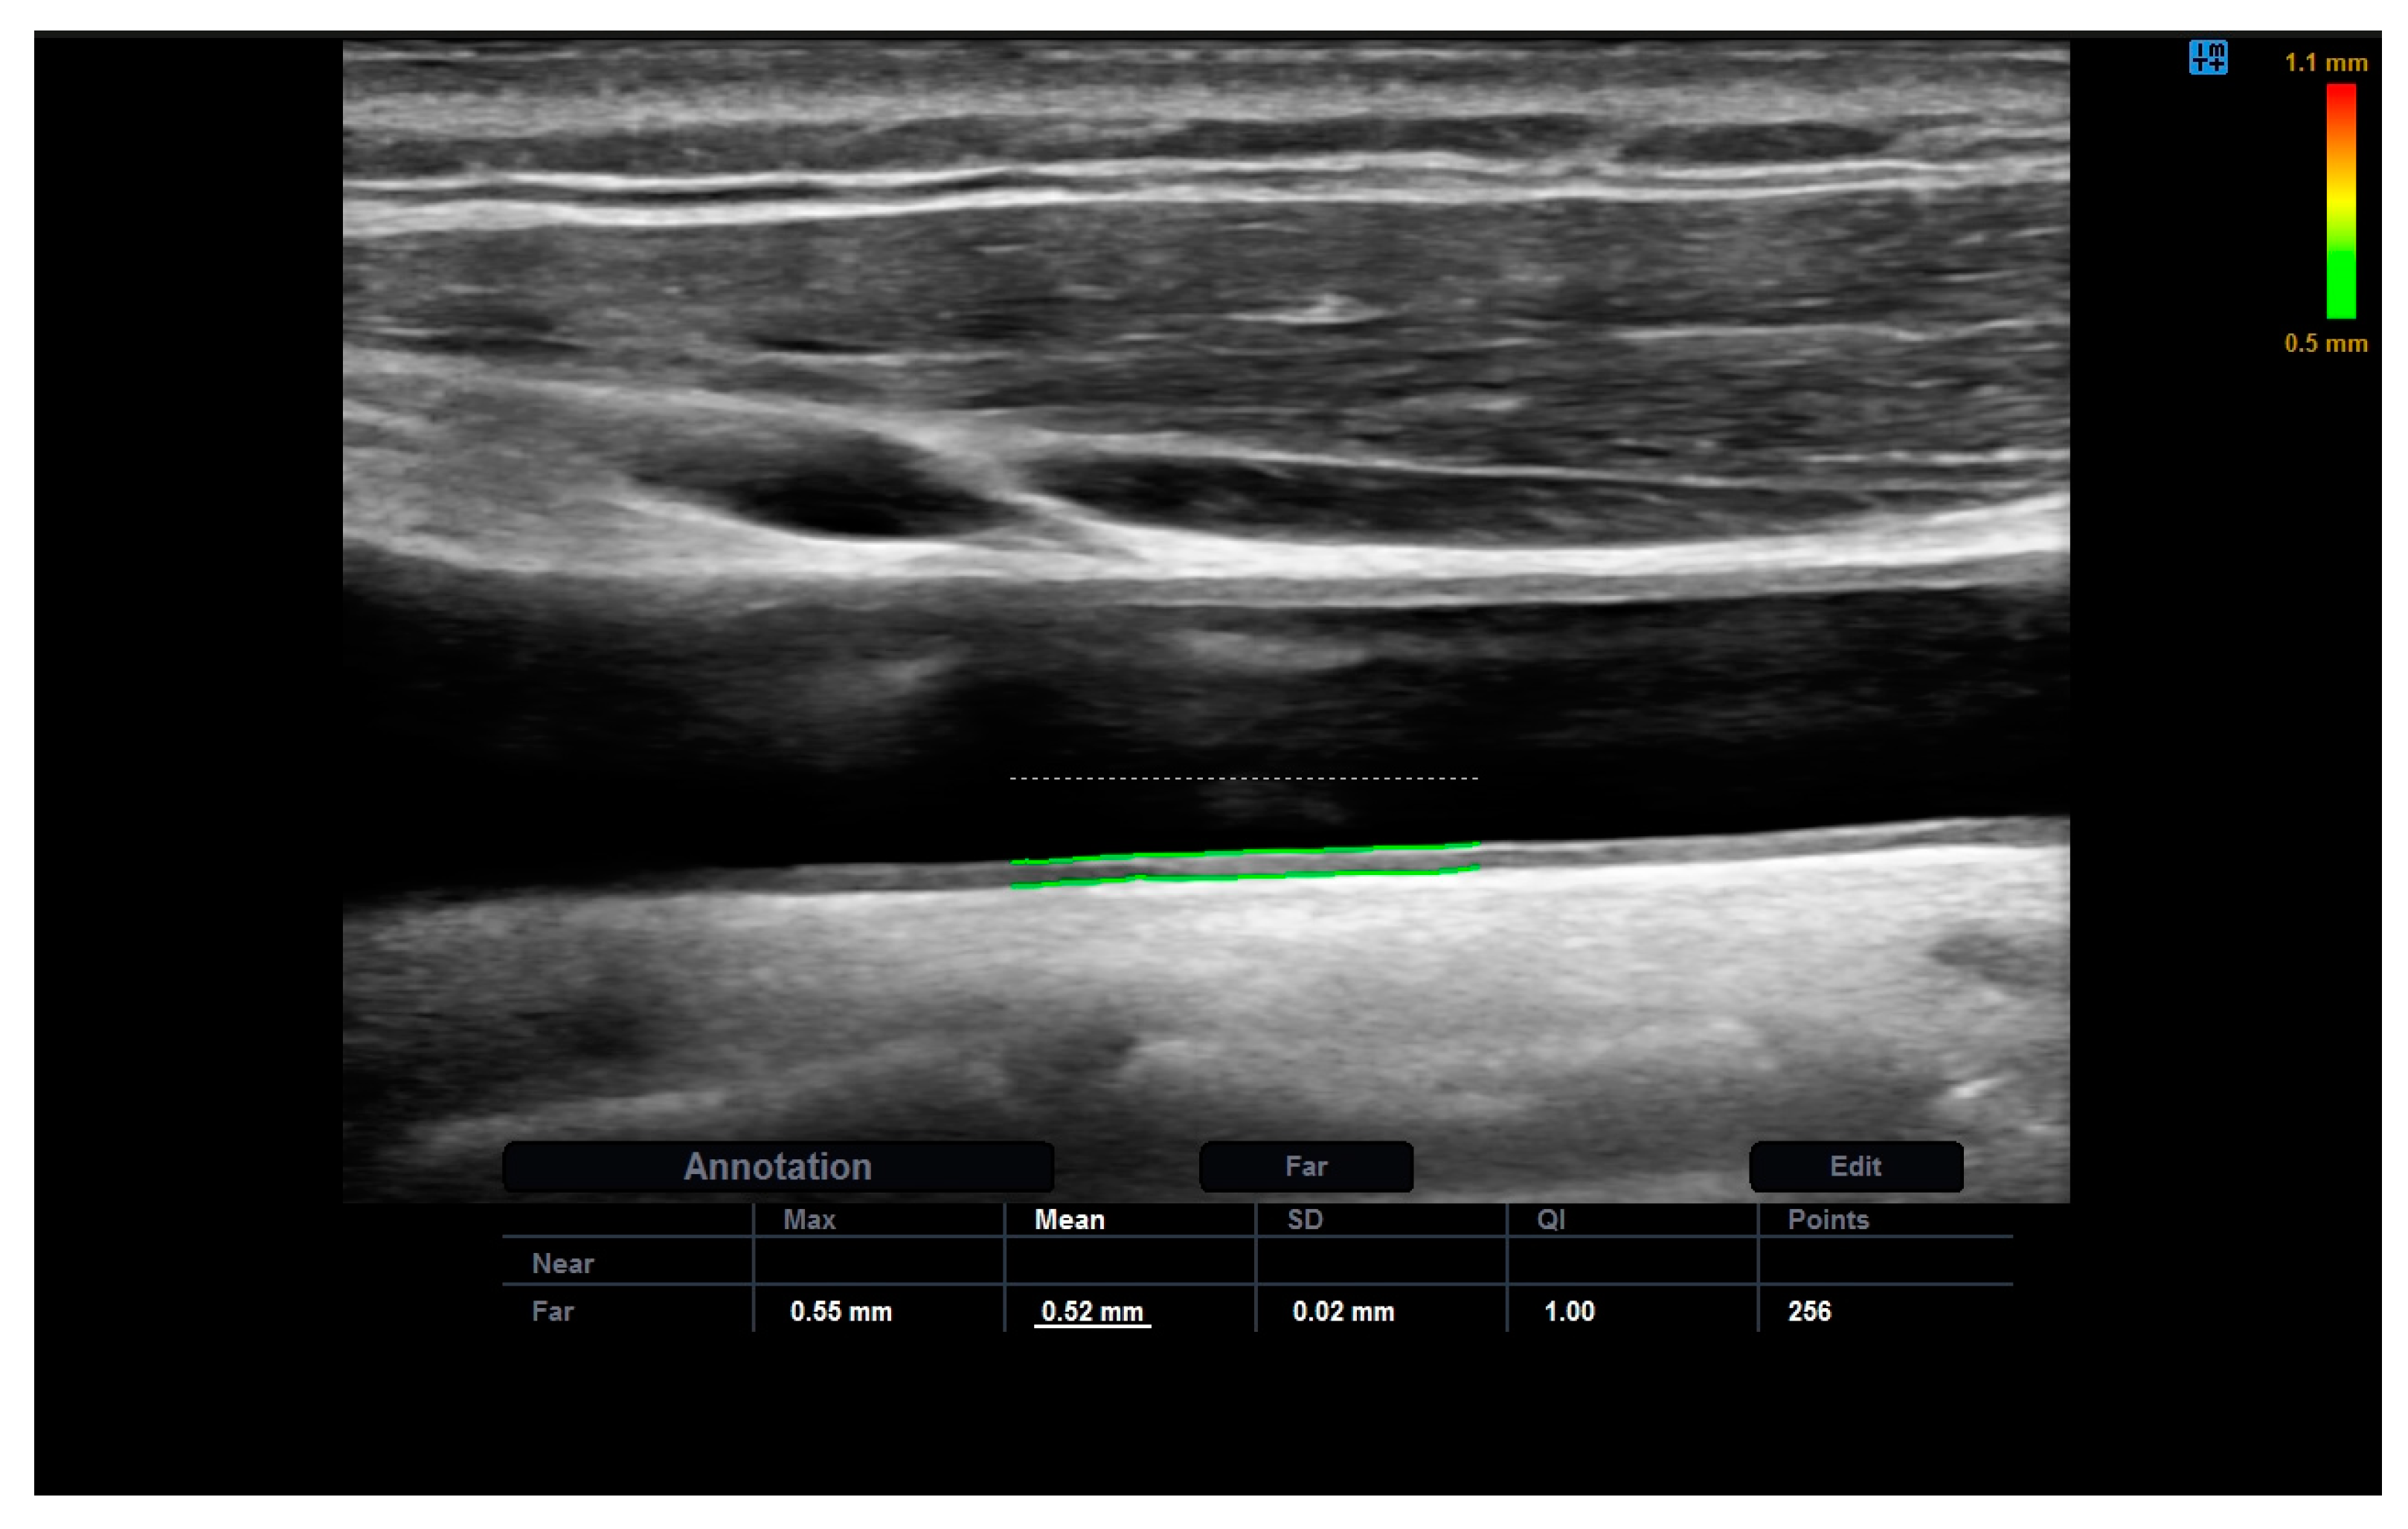

2.3. Carotid and Femoral Ultrasound